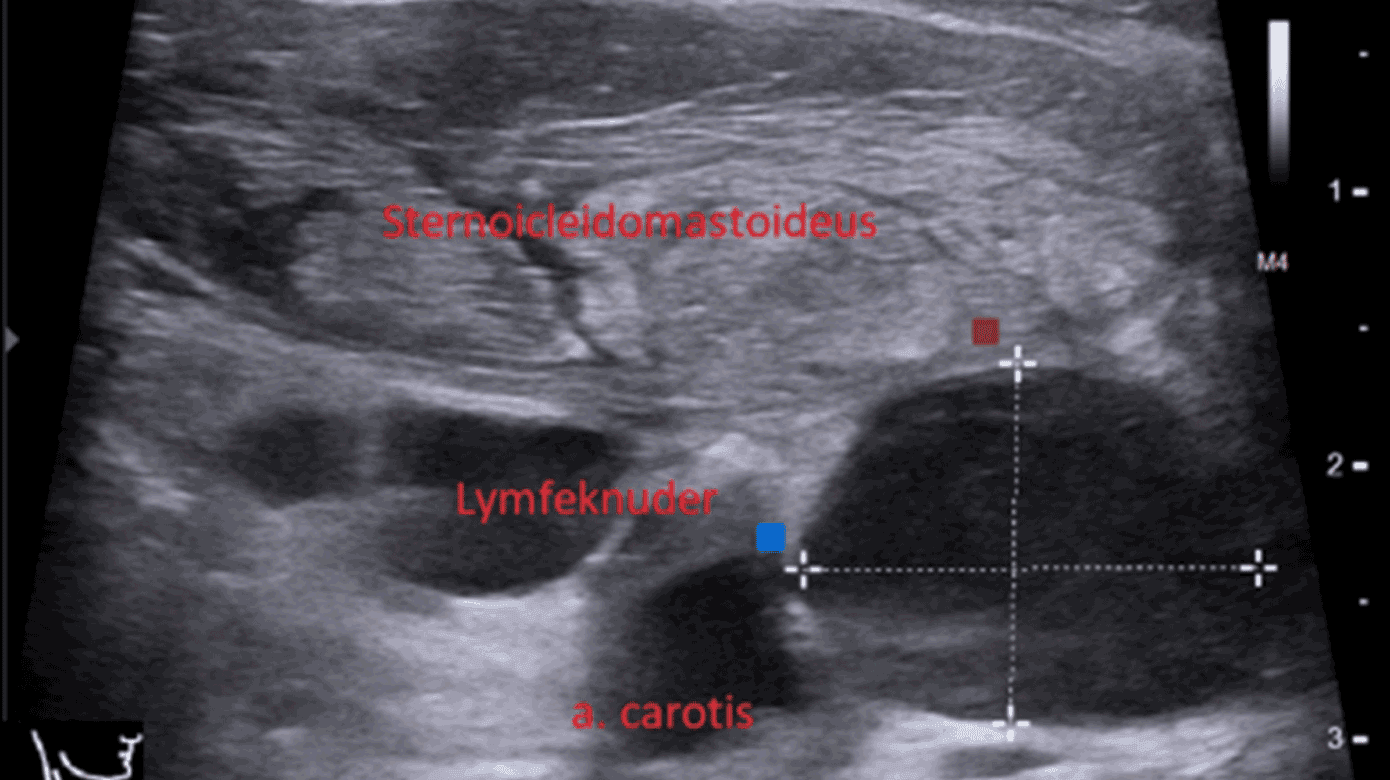

Ved øre-næse-hals-vurdering var tonsillerne højrøde med hvide belægninger, og forholdene i pharynx var symmetriske. På højre side af halsen fandtes en hård, øm hævelse langs forløbet af m. sternocleidomastoideus (SCM). Den overliggende hud var uden rødme. En UL-skanning af halsen viste flegmonøse forandringer i højre SCM og lymfadenitis i højre level 2-4 (Figur 1 A). Temperaturen var 39,1 °C, leukocytniveauet var 24,4 mia./l, og CRP-niveauet var 48 mg/l.

En CT med kontrast af halsen viste udtalt ødem af højre SCM og de omkringliggende bløddele, men ingen absces (Figur 1 B).